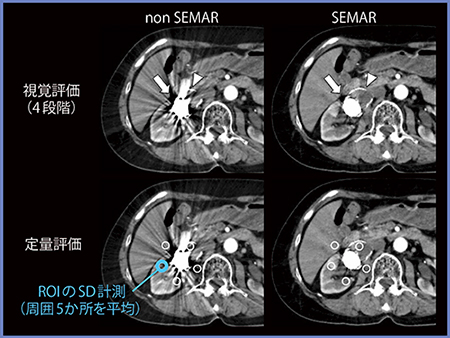

動脈瘤のコイル塞栓術後評価におけるSEMARの役割について,定性評価と定量評価を行った。定性評価は視覚スコア4段階で,定量評価はコイルの周囲に複数のROIを設定してSDを計測し,5か所を平均化して行った(図5)。結果は,定量評価ではノイズはnon SEMAR65±33,SEMAR30±10,アーチファクトは164±55,10±19,定性評価は視覚スコアで1.0±0.0,3.4±0.6と劇的に改善することが確認できた。

図5 動脈瘤のコイル塞栓術後評価におけるSEMARの役割4)